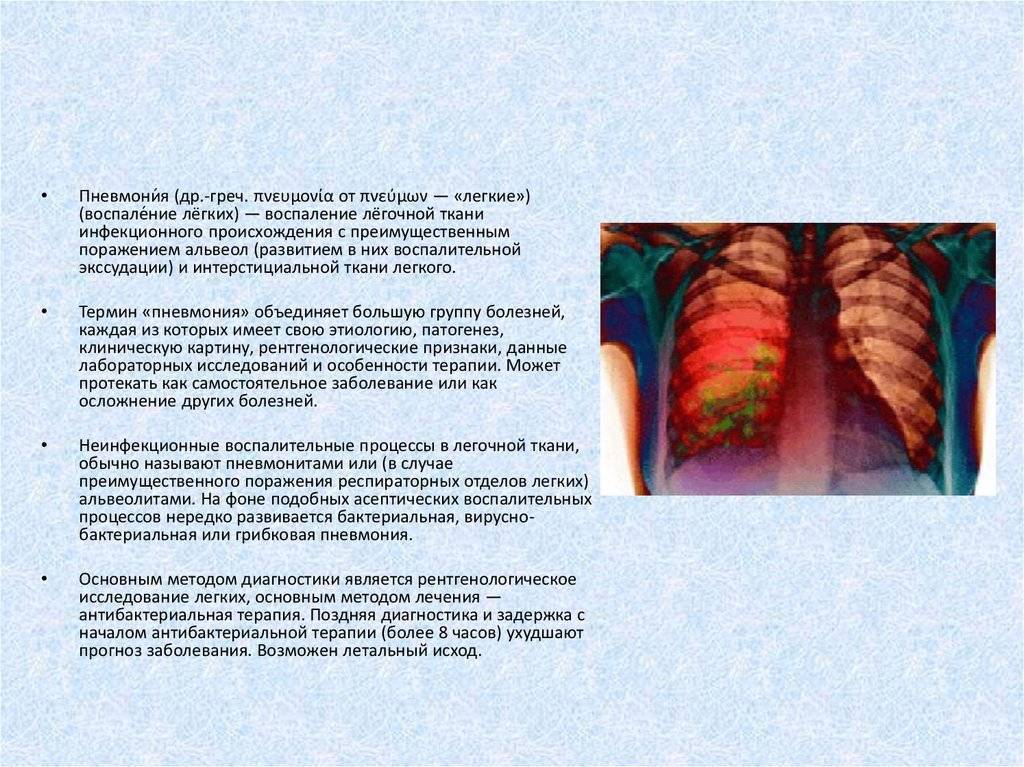

ТАСС-Досье. Пневмония (или воспаление легких) — острое респираторное инфекционное заболевание, вызывающее поражение легочной ткани. Несмотря на то, что заболевание распространено повсеместно, в наибольшей степени, по данным Всемирной организации здравоохранения (ВОЗ), от него страдают дети и семьи в странах Южной Азии и Африки (южнее пустыни Сахара).

Пневмония может протекать в острой, подострой (затяжной) или хронической формах, в тяжелых случаях не исключен смертельный исход. Смешанная вирусно-бактериальная инфекция отягощает течение болезни. В зависимости от вовлеченности легких в воспалительных процесс выделяют одностороннюю (когда поражено одно легкое) и двухстороннюю (оба легких) пневмонию.

Пневмонию могут вызывать различные микроорганизмы: преимущественно бактерии (пневмококки, гемофильная палочка, стафилококки, стрептококки и др.), вирусы (гриппа, респираторно-синцитиальный вирус, риновирусы, аденовирусы и др.), редко грибки и паразиты (аскариды, стронгилоиды и др.).

Основное лечение заболевания — медикаментозное. Назначаются антибиотики в виде таблеток, внутримышечно или внутривенно (в зависимости от тяжести заболевания), антибактериальные и противогрибковые препараты (при выявлении бактериальной или грибковой инфекции). При необходимости больному прописываются иммуностимуляторы, муколитические и отхаркивающие препараты, витамины. Если возникает необходимость, могут назначаться ингаляции кислорода. В большинстве случаев при пневмонии необходима госпитализация пациента в стационар — отделение терапии или пульмонологии.